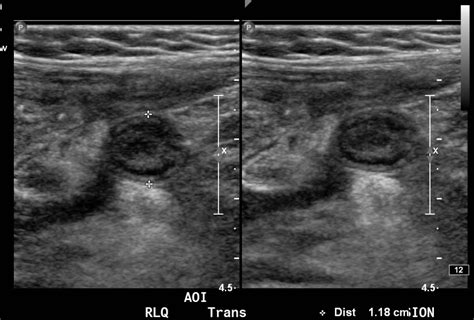

When performing an ultrasound to diagnose appendicitis, radiologists look for several key signs:

• Appendiceal Diameter: A normal appendix is typically less than 6 mm in diameter. An inflamed appendix will often be larger than 6 mm.

• Appendiceal Wall Thickness: The wall of the inflamed appendix may appear thicker than normal.

• Appendicoliths: These are small, calcified stones that can be seen within the appendix on ultrasound. Their presence can indicate a higher risk of appendicitis.